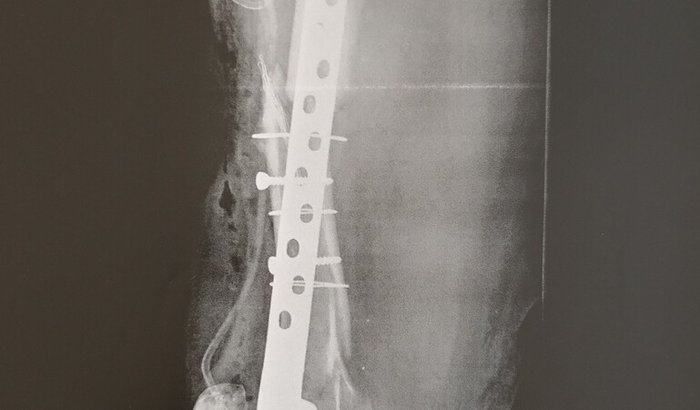

Em julho de 2024, passei por mais uma cirurgia importante, onde foi realizado enxerto ósseo e colocação de placa com parafusos, na tentativa de fazer o fêmur consolidar, naquele momento pensei q minha vitória estava perto e que em poucos meses teria minha vida de volta.

Infelizmente, mesmo com todos esses procedimentos, o osso não cicatrizou como deveria.

Desenvolvi uma pseudoartrose, ou seja, o fêmur não consolidou.

Hoje dependo de muletas para conseguir andar,  não posso apoiar e nem pisar com  minha perna direita pois a placa quebrou, sinto dor e enfrento limitações diariamente.